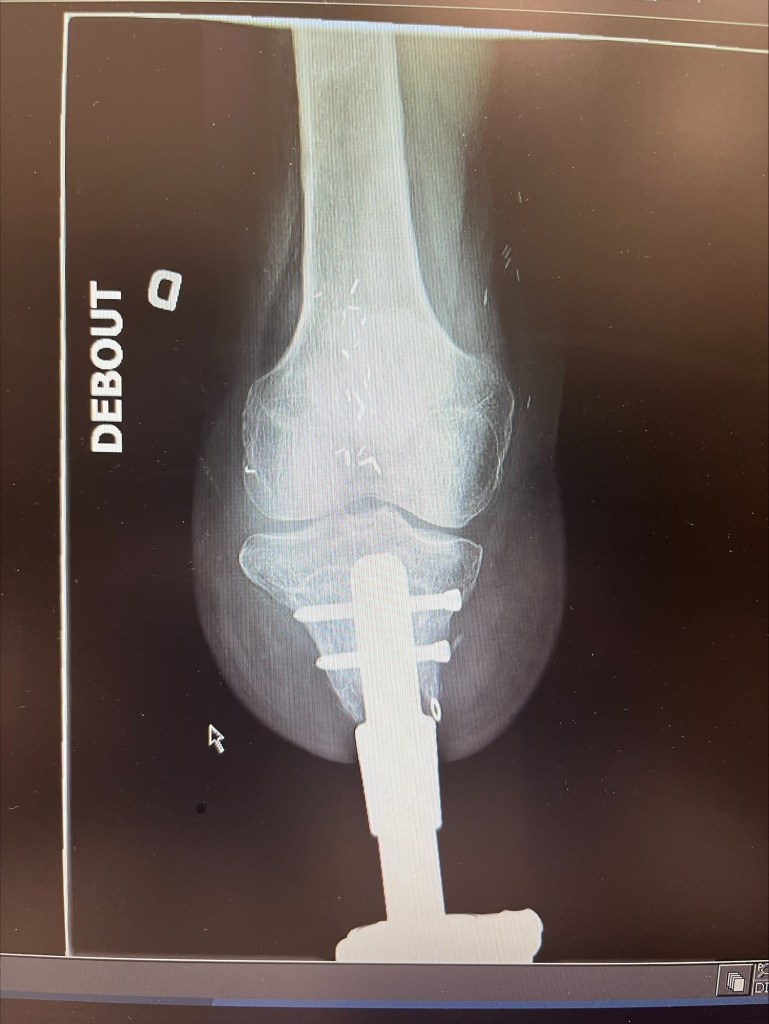

On a allongé mon tibia, puis on y a ancré une tige, solide, profonde, jusqu’au genou. Un geste chirurgical… mais aussi un acte de confiance envers l’avenir. Et malgré tout ce que mon corps endure, elle, tient bon.

Voici ma radiographie. On peut voir que ma tige est branchée à ma prothèse.